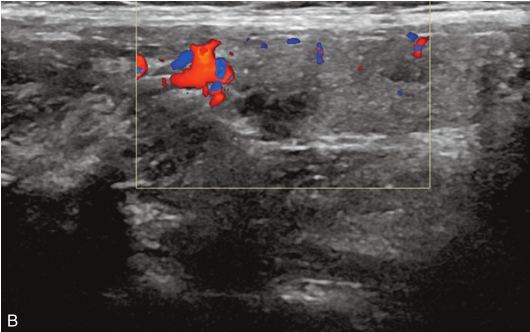

甲状腺右叶中部可见一个肿块,大小约为2.6cm×1.8cm×1.8cm,形状尚规则,边界尚清楚,内部为低回声,分布不均匀,后方回声无变化,CDFI显示肿块内可见丰富的血流信号,见图1-9-1。

图1-9-1 甲状腺髓样癌常规超声图像

A.甲状腺右叶低回声结节纵切面灰阶超声图像;B.甲状腺右叶低回声结节横切面灰阶超声图像;C.CDFI图像